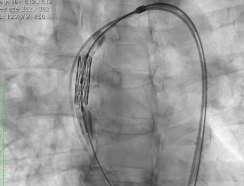

Navigator with Myval THVNavigator balloon with dual expansion ports at each end ensures rapid, simultaneous, controlled expansion (dog-boning) of distal and proximal ends

This typical dog bone pattern of inflation steadies the valve during expansion phase, ensuring its precise annular position and deployment without any risk of valve migration